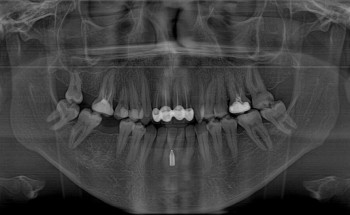

مستشفى الدكتور سليمان الحبيب بالقصيم يجري جراحة ناجحة لشاب كويتي بإزالة ورم بالمخ بعد أن أصيب بمرض NF2 الذي أفقده القدرة على الحركة

نجح مستشفى الدكتور سليمان الحبيب بالقصيم في إنقاذ حياة شاب كويتي يبلغ من العمر 18 عامًا، بعد إجراء الفريق الطبي جراحة خطرة في المخ؛ بسبب إصابته بمرض نادر NF2، والذي أدى لتجمع عدة أورام على ...